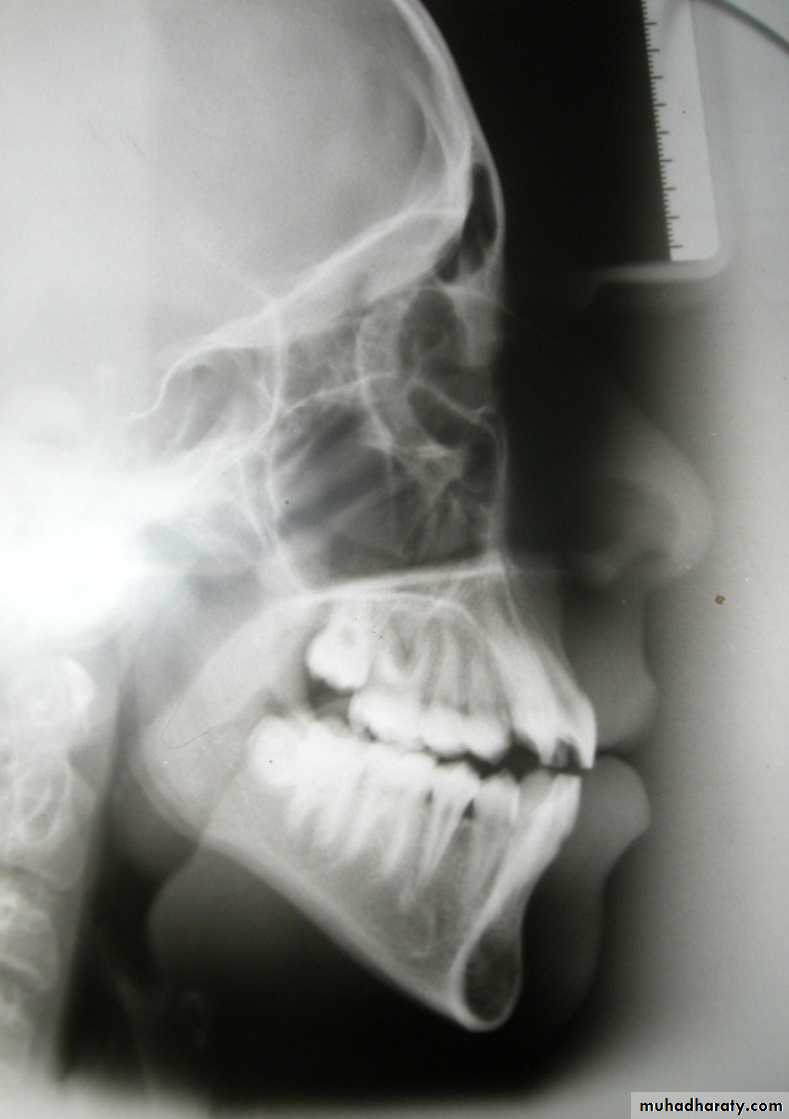

Cephalometric assessment

Cephalometric lines of reference

1. True horizontal:

Can be identified when the patient’s head is in the natural postural position, this line is differ from one person to other.

2. Frankfort plane:

Po - Or

3. Sella - Nasion plane:

S - N

4. De Coster’s line:

The floor of the anterior

cranial base, from ethmoid

bone to sella turcica

5. Maxillary line:

ANS - PNS

6. Mandibular plane:

Me - Go

7. Occlusal plane:

Cusp tips of molars – tip of lower incisor

8. Functional occlusal plane (FOP):

Cusp tip of lower 1st molar –

cusp tip of lower 1st premolar

9. The facial plane:

N - Pog

10. Line from point A to pogonion:

A - Pog